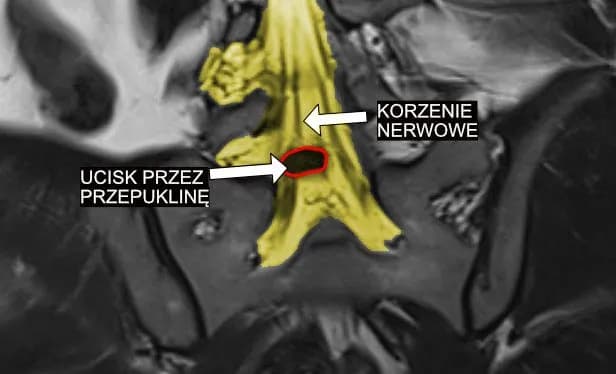

- Diagnozę stawia się na podstawie badań obrazowych i EMG

Objawy zapalenia splotu nerwowego rozpoczynają się zwykle od uczucia mrowienia i drętwienia. Następnie pojawia się charakterystyczny, pulsujący ból, który może promieniować wzdłuż przebiegu nerwu. G54 zaburzenia czucia objawy często nasilają się w nocy lub podczas wykonywania określonych ruchów. W początkowej fazie choroby pacjenci mogą odczuwać także osłabienie mięśni w okolicy objętej schorzeniem.